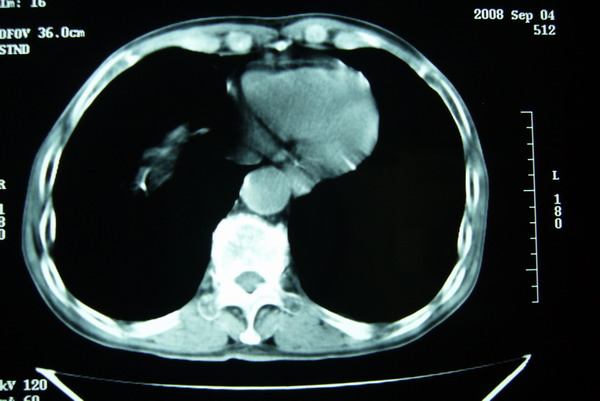

标题: CT15579:男 86岁 咳嗽 咳少量白痰 发热2天 吸烟史60年 [打印本页]

标题: CT15579:男 86岁 咳嗽 咳少量白痰 发热2天 吸烟史60年

右上周围型肺癌,慢支,肺气肿。

分叶及少量边缘性钙化,老年人,周围性肺癌首先考虑。

右肺上叶巨大软组织肿块,轮廓不规则,纵隔内有肿大淋巴结,首先考虑肺癌。

右上肺一不规则团块,边缘有分叶和毛刺,纵隔有淋巴结肿大。右肺周围性肺癌首先考虑。